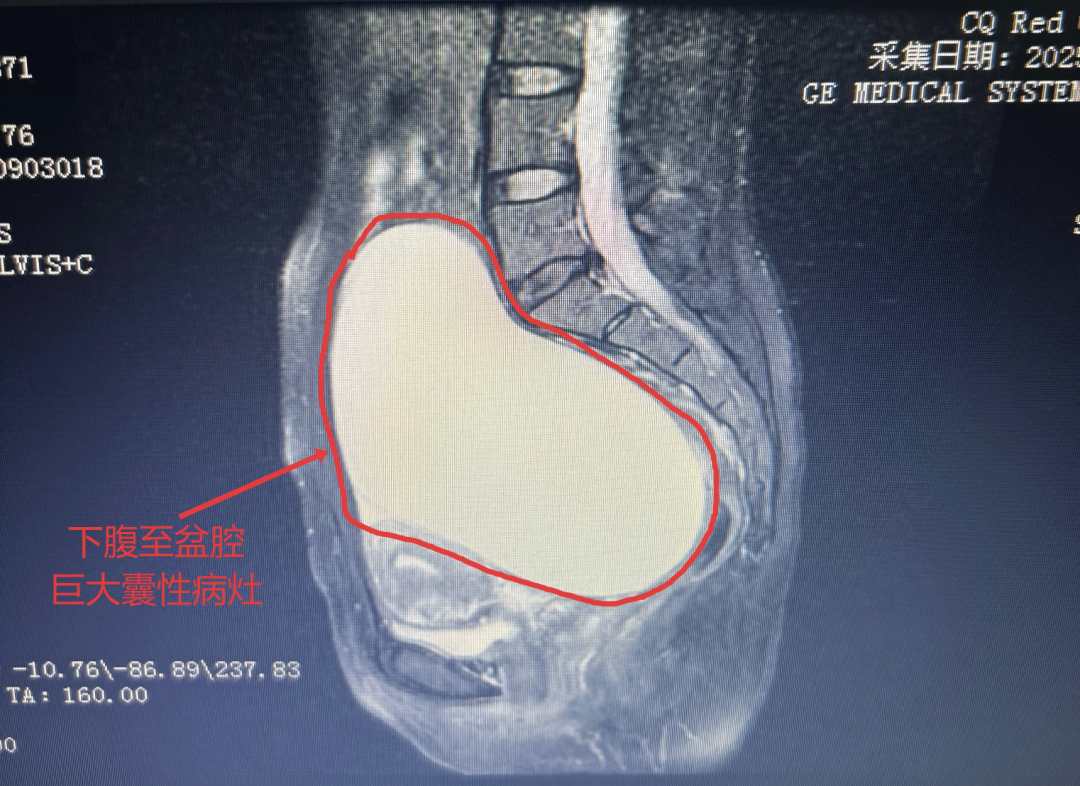

患者谭女士,39岁,因下腹胀痛在我院就诊。经检查,盆腔MRI提示下腹至盆腔巨大囊性占位,结合病史及辅助检查,诊断为卵巢囊肿。患者包块巨大,引起腹胀不适,需尽快手术治疗。